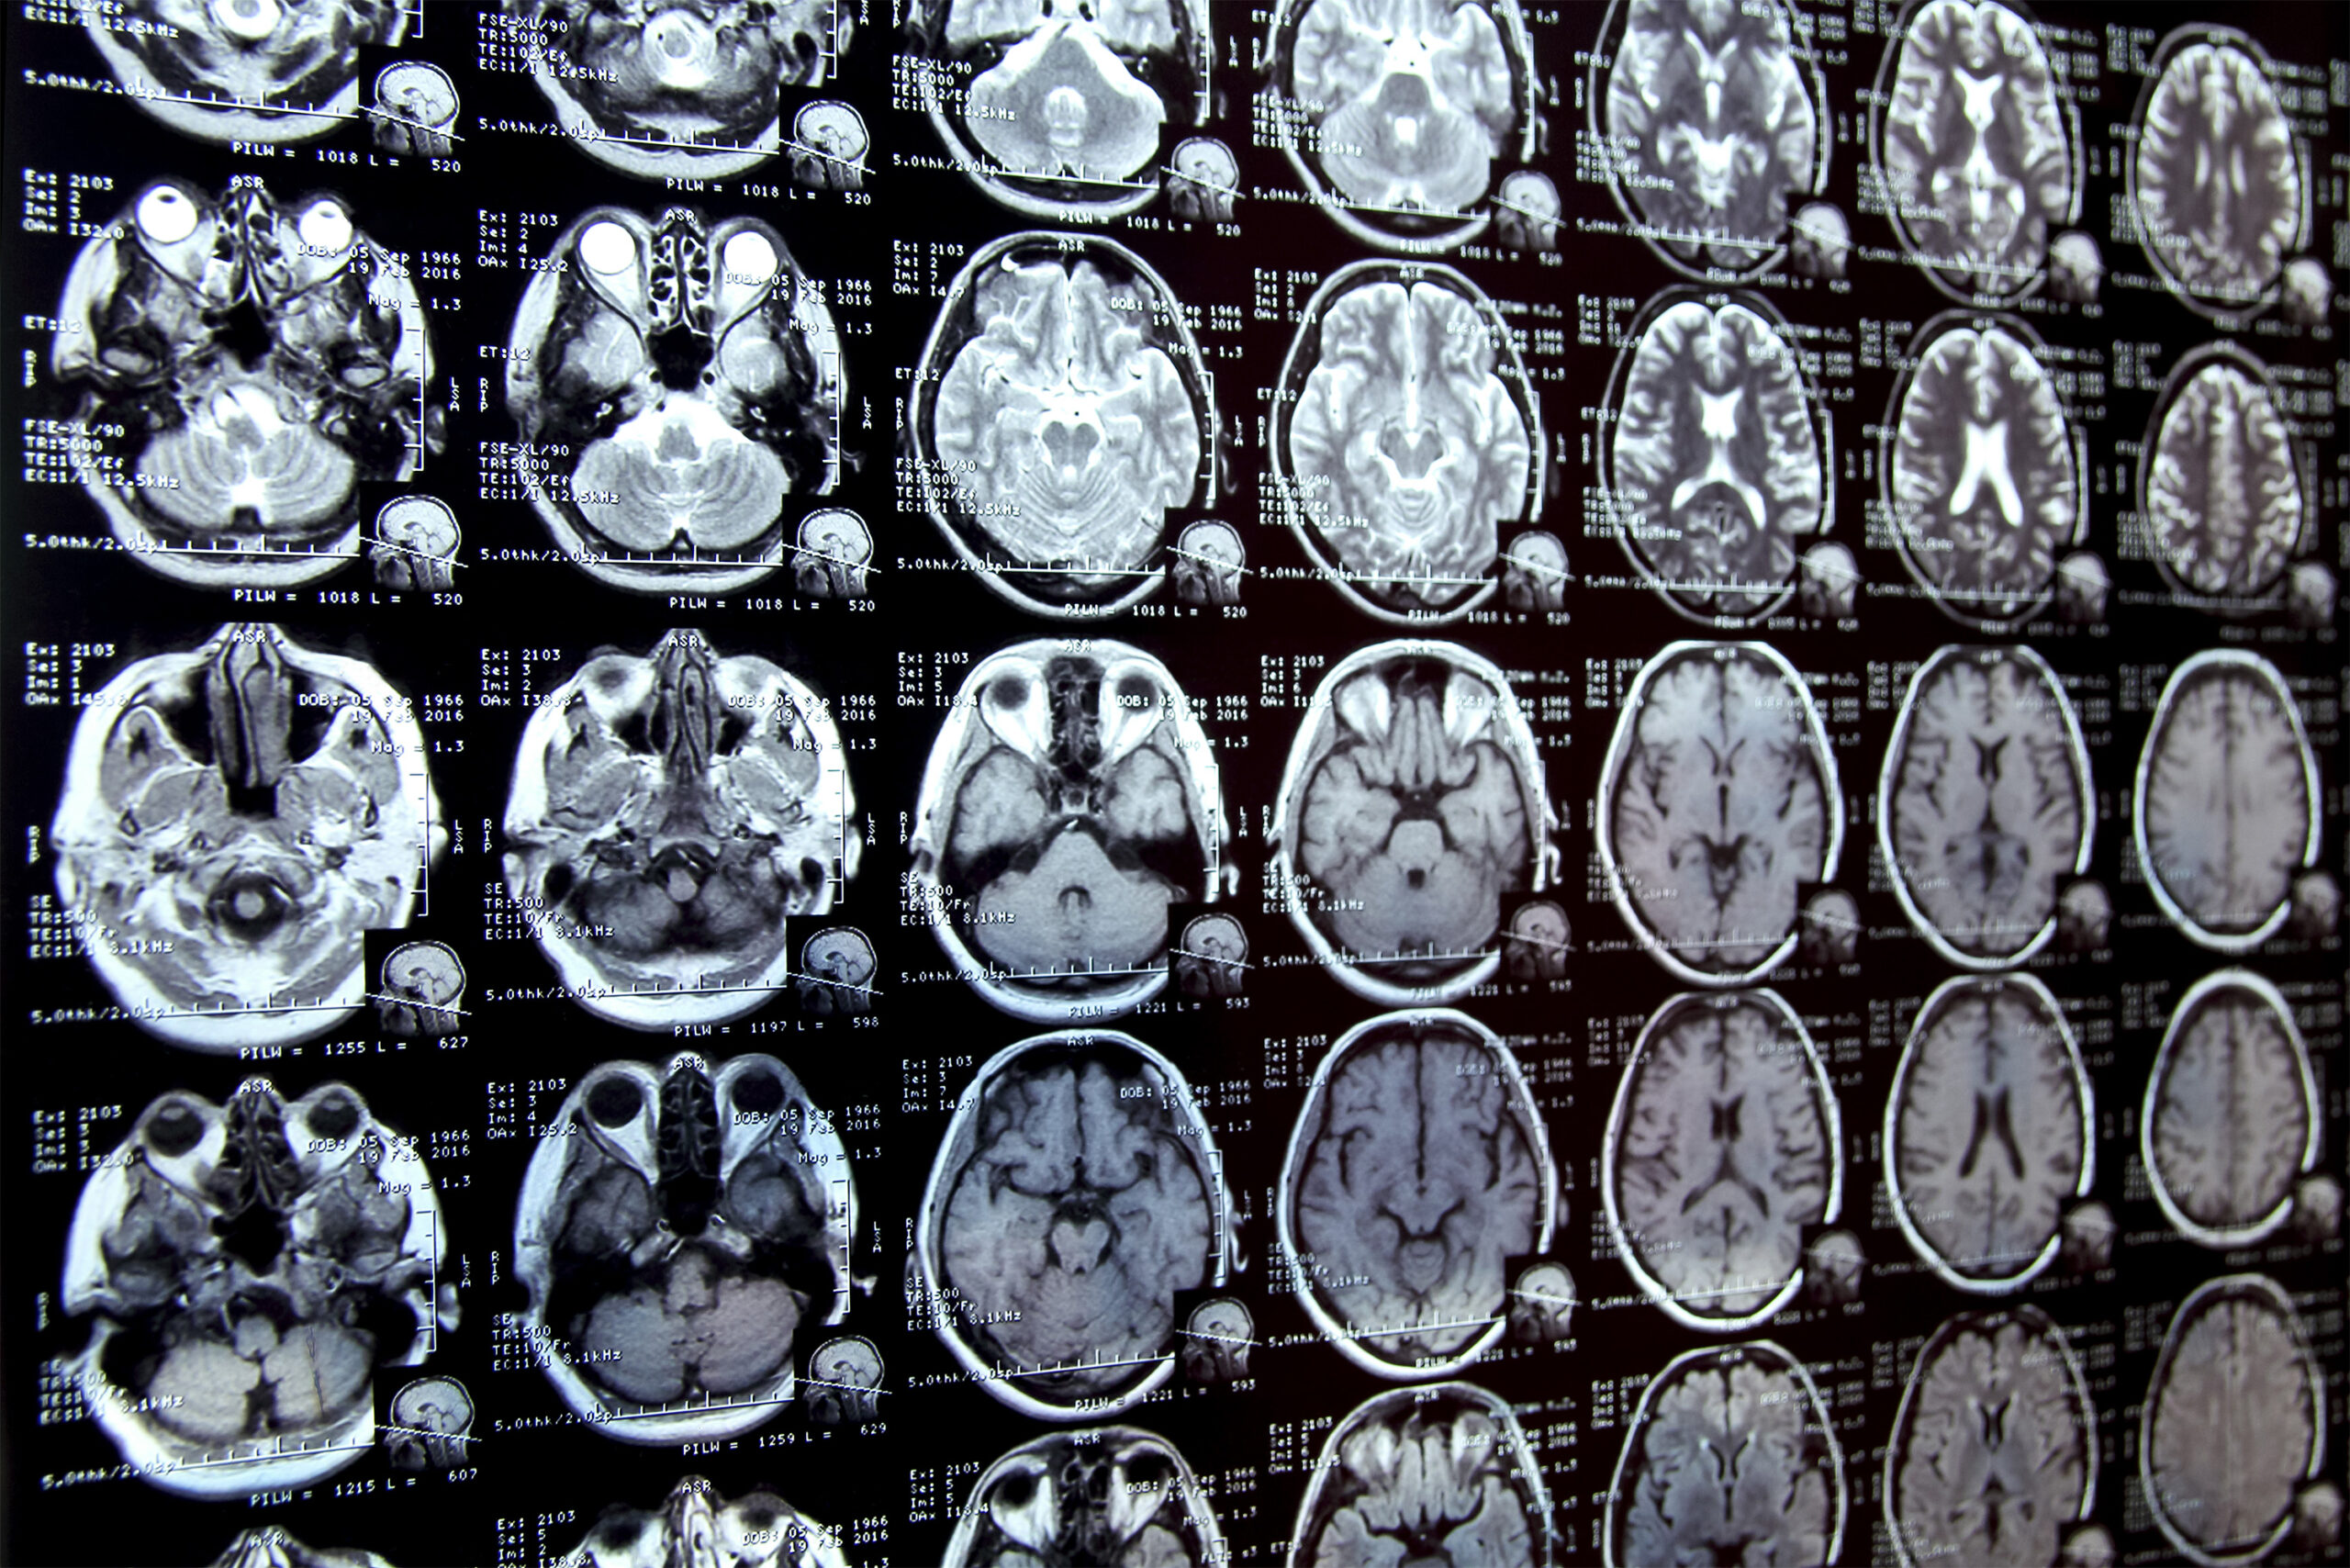

Um beispielsweise zu bestimmen, wie sich die Größe des Hippocampus des Gehirns im Alter von Patienten verändert, skizziert der Wissenschaftler zunächst jeden Hippocampus in einer Reihe von Gehirnscans. Für viele Strukturen und Bildtypen ist dies häufig ein manueller Vorgang, der extrem zeitaufwändig sein kann, insbesondere wenn die untersuchten Regionen eine Herausforderung für die Größenordnung sind.

Es gibt hauptsächlich zwei Methoden, die Forscher verwenden, um neue Sätze von medizinischen Bildern zu segmentieren. Bei der interaktiven Segmentierung geben sie ein Bild in ein AI -System ein und verwenden eine Schnittstelle, um Bereiche von Interesse zu markieren. Das Modell prognostiziert die Segmentierung basierend auf diesen Interaktionen.

Bei einigen Bildtypen wie Röntgenstrahlen muss der Benutzer möglicherweise nur ein oder zwei Bilder manuell segmentieren, bevor das Modell genau genug wird, um selbst Vorhersagen zu treffen.